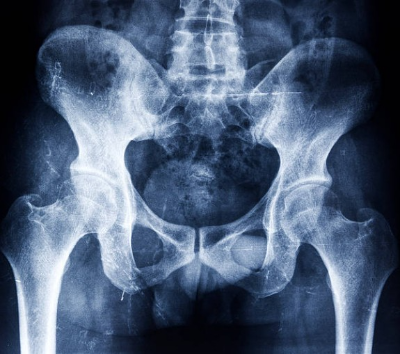

외상이나 부상을 입은 경우에는 즉시 의사의 진단과 치료를 받아야 합니다. X-선, MRI, CT 등의 검사를 통해 꼬리뼈의 손상 정도를 확인하고, 적절한 치료법을 선택하시면 됩니다.

임신이나 출산으로 인한 꼬리뼈 통증은 대부분 일시적이고 자연스럽게 회복됩니다. 하지만 통증이 심하거나 지속되면 전문가의 도움을 받아야 합니다. X-선, MRI, CT 등의 검사를 통해 꼬리뼈의 상태를 확인하고, 적절한 치료법을 선택하시면 됩니다.

기타 질환으로 인한 꼬리뼈 통증은 해당 질환의 원인과 증상에 따라 다른 치료법을 적용해야 합니다. 그러므로 가능하면 전문가의 진단과 치료를 받으시는 것이 좋습니다. X-선, MRI, CT 등의 검사를 통해 꼬리뼈와 관련된 질환의 유무와 정도를 확인하고, 적절한 치료법을 선택하시면 됩니다.